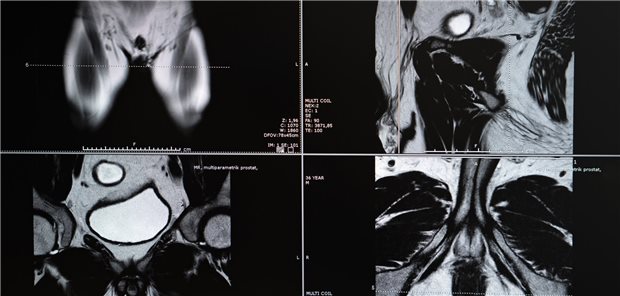

Die Ärztinnen und Ärzte um Nordström bestimmten den PSA-Wert der Patienten, lag dieser über 1,5 ng/ml, erfolgte die Bestimmung des STHLM3-Scores. War auch dieser erhöht oder lag der PSA über 3 ng/ml, ordneten sie eine weitere Untersuchung an – entweder gleich per Biopsie (Kontrollgruppe) oder erst per MRT, und dann gegebenenfalls per Biopsie.

© bfk92 / Getty Images / iStock

Anhaltend hohe PSA-Werte

Wiederholtes Prostatakrebs-Screening per MRT ist überflüssig